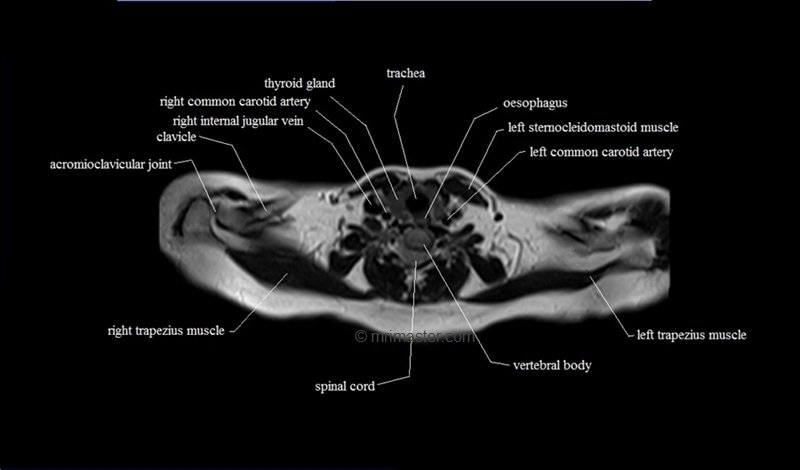

MRI Axial Cross Sectional Anatomy of Chest

This MRI chest (thorax) axial cross sectional anatomy tool is absolutely free to use. Use the mouse scroll wheel to move the images up and down, or alternatively, use the tiny arrows (→) on both sides of the image to navigate through the images. For a more detailed view, double-click the image to view it in full screen, and use the menu in the top right-hand corner to view individual slides or play them in a loop.